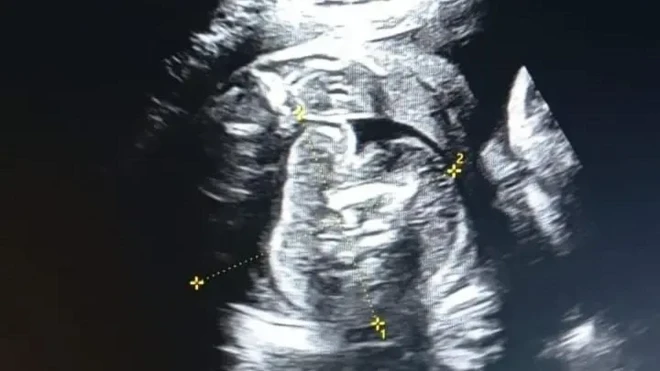

Waxay sheegtay inay xoogga saartay xagga waxbaridda howlwadeennada caafimaadka ee haweenka ah, sida loo gacan qabto hooyada marka ay foolanayso haddii ay ku yimaadaan dhiig-bax ama kalamasiyo.

"Abaalmarinta waxaa la igu siiyey shaqadii is-xilqaanka ah ee aan isku xil-qaamay inaan hooyooyinka isku dhimanaya markay foolanayaan sidii loo kala badbaadi aan cilmigeedii baro umulisooyinka, dhaqaatiirka iyo kalkaaliyaasha ka shaqeeya qaybta hooyooyinka iyo dhalaanka,"ayey intaas raacisay Ayaan.